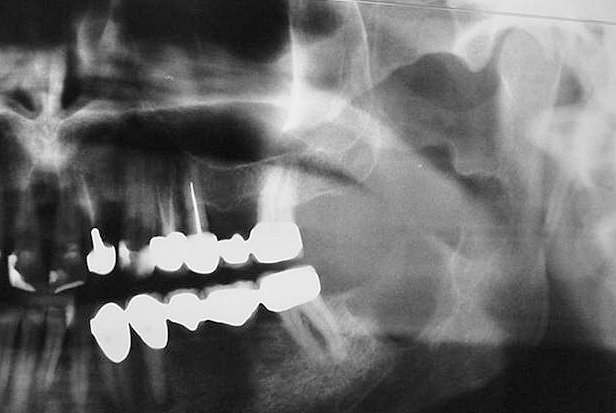

Περιστατικό 1

Περίπτωση οδοντογενούς κερατινοκύστης στην πρόσθια περιοχή της κάτω γνάθου.

• Συνηθέστερη εντόπιση: γομφιακή χώρα, γωνία και κλάδος της κάτω γνάθου.

• Η αλλοίωση μπορεί να αποκτήσει μεγάλο μέγεθος. Εκτείνεται συχνά κατά μήκος του σώματος της κάτω γνάθου προκαλώντας λέπτυνση ή και διάτρηση των οστικών πετάλλων.

• Οι μικρές βλάβεις είναι συνήθως μονόχωρες, ενώ οι μεγάλες βλάβες πολύχωρες με την ακτινογραφική εικόνα είτε φυσσαλίδων από σαπούνι είτε κερήθρας.

• Τα όρια της αλλοίωσης είναι σαφή, καλά καθορισμένα και ορισμένες φορές περιγράφονται ως ‘δαντελωτά’.